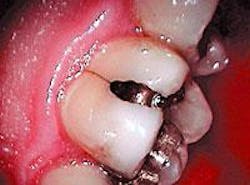

This, however, is not a technique article, friends. The troubling issue is that decay is not being removed. Why? Two reasons: old technique holdover and vision.

Regarding posterior composites, all - and I mean all - decay and soft dentin and decalcified enamel must be removed. This is a zero-tolerance consideration!

There is no toxic biofilm to save you here. Bonding has to be precise! Bonding over an unknown micro-junk pile - similar to current "sealant" theory - is a fantasy fix. No amount of sixth - or any generation - agent will help you, nor will a high-output laser help you. You are on your own, chum!